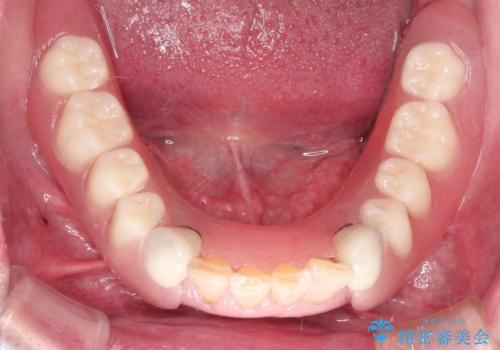

上顎は全体的にクラウンの入れ替えと、下顎はインプラントの提案もしましたが、希望されなかったのでノンクラスプデンチャーの製作をする治療計画としました。

お忙しい方でしたので、治療が終了するまでにじかんがかかってしまいましたが、奥歯でもしっかり咬めるようになったと喜んでいただけました。